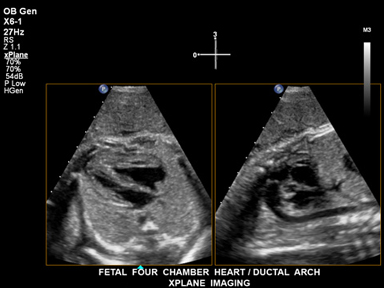

L'imaging Live xPlane crea contemporaneamente due piani di imaging a piena risoluzione, in modo da catturare una quantità di dati clinici doppia nello stesso intervallo di tempo dell'imaging 2D convenzionale.

Le informazioni aggiuntive prodotte dall'imaging Live xPlane mostrano due viste delle quattro camere cardiache del feto e dell'arco duttale.